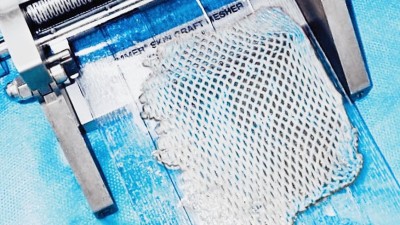

Marek stále neměl vyhráno, po amputaci jej čekala další operace ruky a druhé nohy. „Domů jej pustili 17. září, tedy měsíc po nehodě. Teď se učí být samostatný, rehabilituje. To vše stojí mnoho peněz, byli bychom šťastní, kdyby mohl získat kvalitní protézu, aby se mohl zase postavit na obě nohy," uzavírá Martina Vítková.